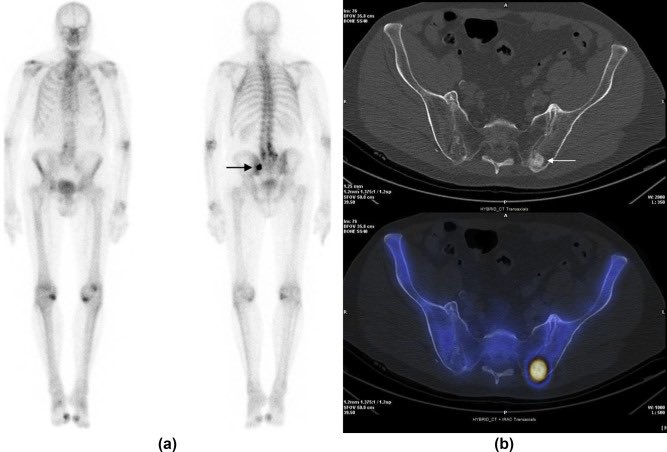

(SPECT) تصوير مقطعي محوسب باستخدام فوتون واحد وفيه يتم استخدام القاما كاميرا وجهاز الاشعة المقطعية للحصول على صور تشخيصية تحتوي على النشاط الفسيولوجي مع وضوح التشريح الداخلي للاعضاء .

من اهم استخداماته : امراض الدماغ والقلب والعظام والغدد الصماء وغيرها .